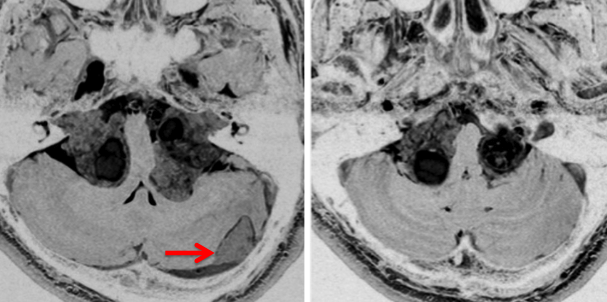

中心となるのは神経鞘腫と髄膜腫です。下のMRIは典型的な両側聴神経腫瘍と呼ばれる画像です。両側の内耳道から腫瘍(黒く見えるもの)が突出して,脳幹部を強く圧迫しているために脳幹部が縦長に変形してしまっています。この様にひどい脳幹部変形でもほとんど症状が無く暮らしていた患者さんです。赤い矢印で示すのは横静脈洞内から突出している髄膜腫です。